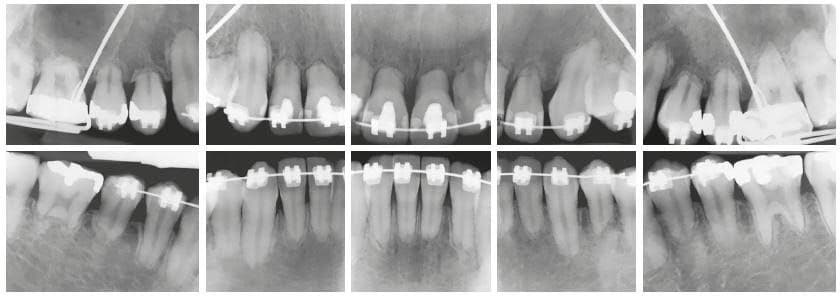

การศึกษาที่ผ่านมาได้พยายามหาปัจจัยที่สัมพันธ์กับการทำให้เกิดการละลายของรากฟันจากการรักษาทางทันตกรรมจัดฟัน พบว่าภาวะรากฟันละลายมีความสัมพันธ์กับหลายปัจจัย เพื่อป้องกันปัญหาดังกล่าว ทันตแพทย์ผู้ให้การรักษาควรประเมินปัจจัยต่างๆที่เกี่ยวข้องก่อนให้การรักษาจัดฟัน โดยการซักประวัติ การตรวจทางคลินิก และการถ่ายภาพรังสี เพื่อประเมินความเสี่ยงจากปัจจัยต่างๆ เช่น พันธุกรรม โรคทางระบบ ประวัติการได้รับอุบัติเหตุ ฟันที่รักษารากฟันมาก่อน หรือลักษณะของรากฟันที่เสี่ยงต่อการละลายระหว่างจัดฟัน ทันตแพทย์ควรแจ้งถึงความเสี่ยงที่อาจเกิดขึ้นในระหว่างการจัดฟันให้ผู้ป่วยรับทราบ ส่งถ่ายภาพรังสีเพื่อประเมินความเสี่ยงเป็นระยะ จากการทบทวนวรรณกรรมได้แนะนำให้ถ่ายภาพรังสีในช่วง 6-12 เดือน ภายหลังเริ่มให้แรงเพื่อประเมินได้ทันท่วงที การหยุดให้แรง 2-3 เดือน ภายหลังพบการละลายของรากฟันจะสามารถลดกระบวนการละลายของรากฟันได้ หากพบการละลายของรากฟันในระดับรุนแรงอาจจำเป็นต้องเปลี่ยนแปลงแผนการรักษาทางทันตกรรมจัดฟัน นอกจากนี้ ในระหว่างการรักษาทางทันตกรรมจัดฟัน ทันตแพทย์พึงระมัดระวังการให้แรงที่มากเกินไป ควรใช้แรงแบบขัดจังหวะ เคลื่อนฟันในปริมาณน้อยที่สุด โดยเฉพาะในผู้ป่วยที่มีความเสี่ยง เพื่อให้การรักษาประสบความสำเร็จและปลอดภัยต่อผู้ป่วย